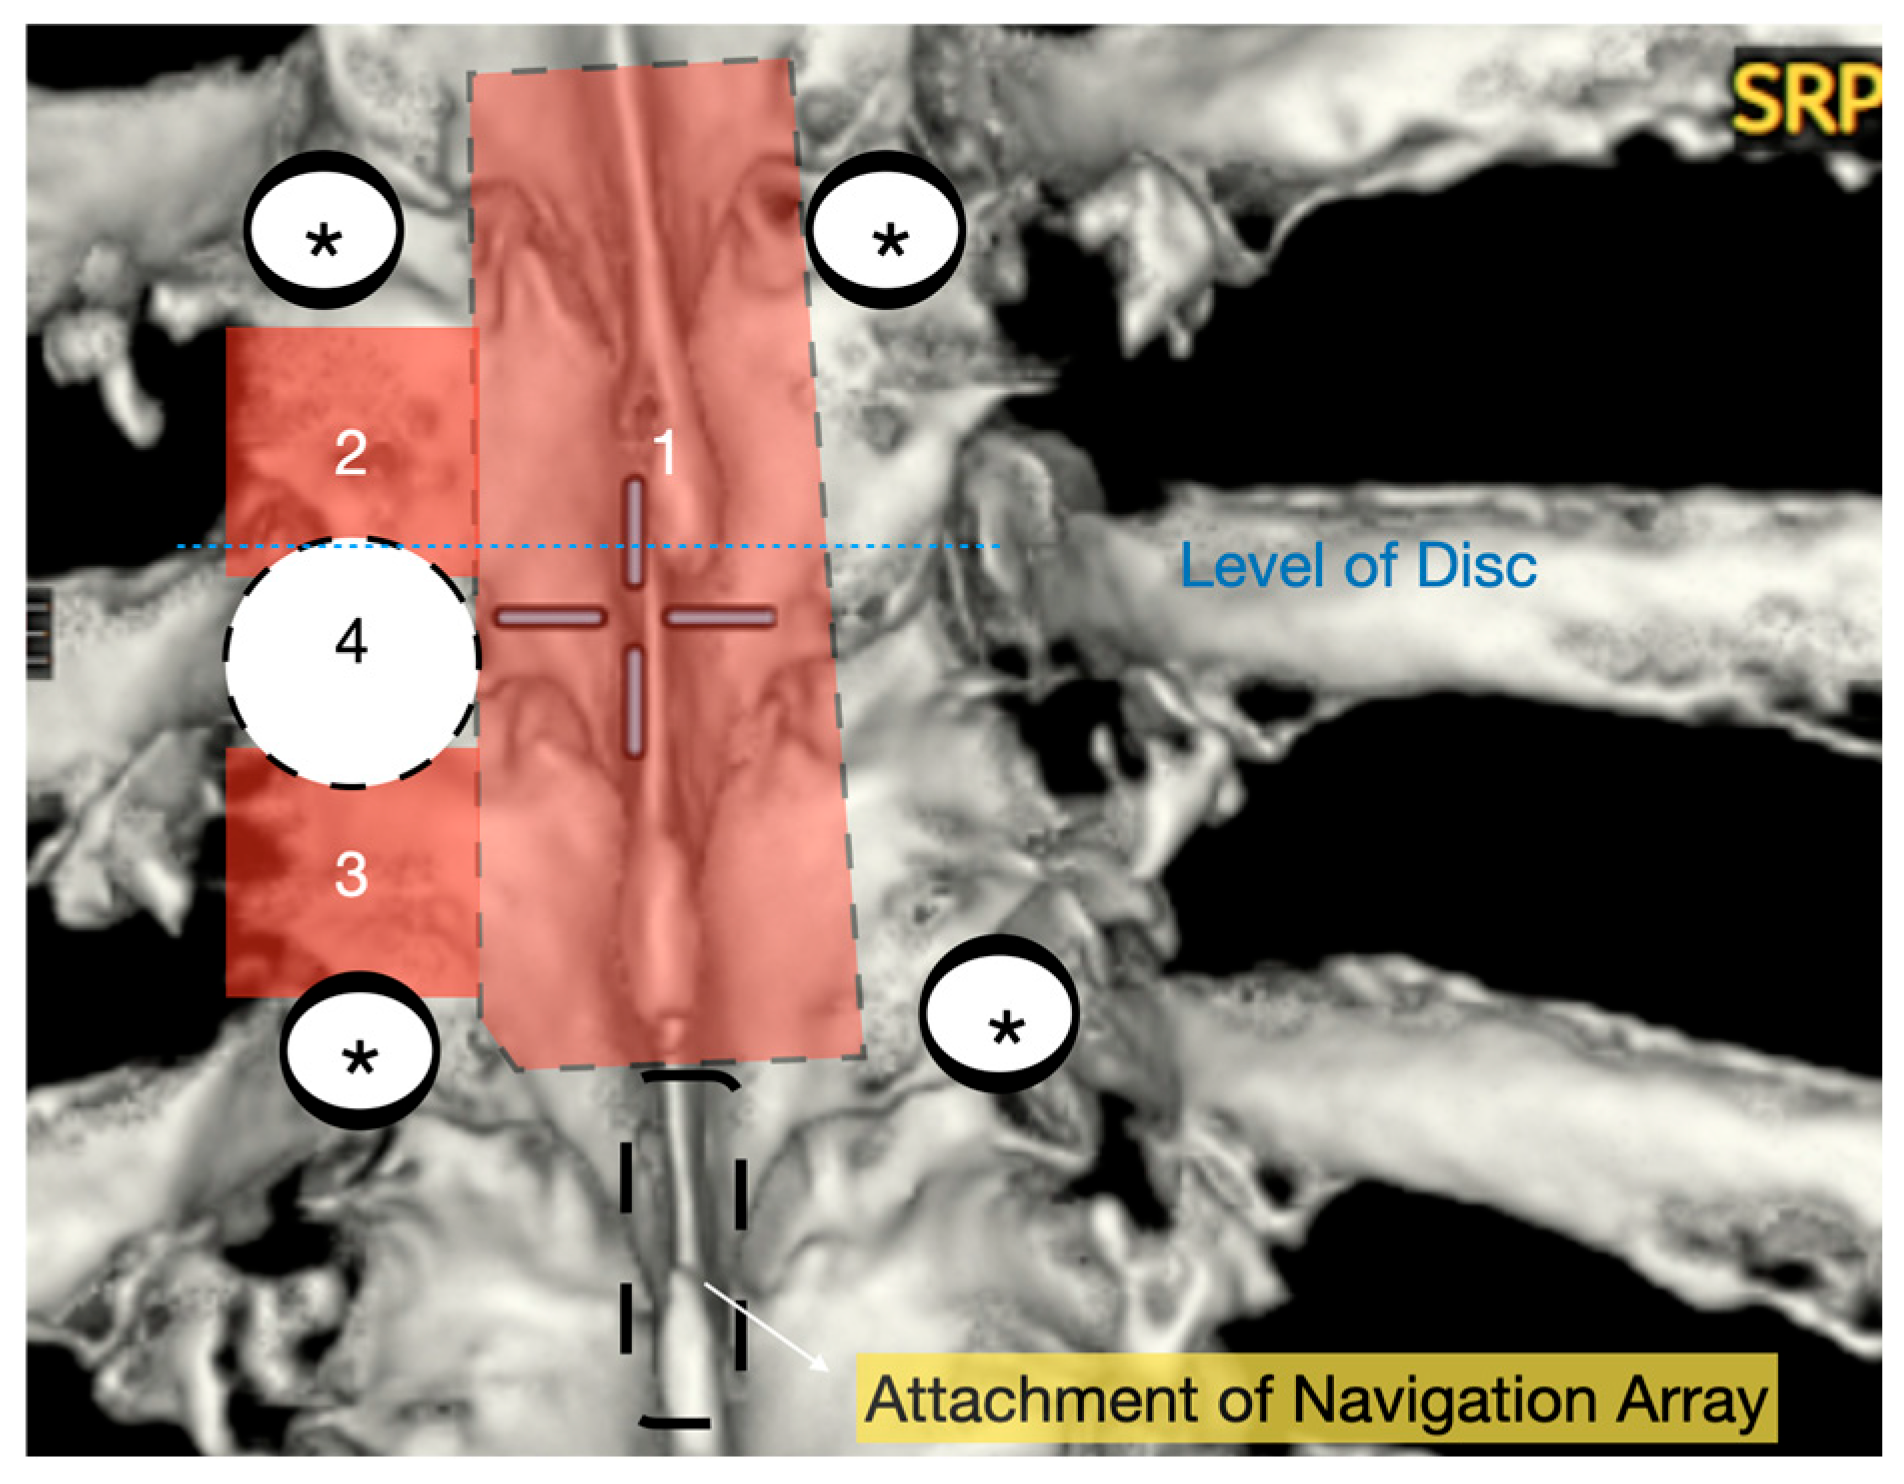

Figure 1. Three-dimensional reconstruction of area of interest (T9–11) with representation of osteotomies carried out with bone scalpel. 1: En block laminectomy; 2: ipsilateral upper facetectomy; 3: ipsilateral lower facetectomy; 4: ipsilateral pediculectomy. *: screws.

Patients were positioned prone on an Allen Table with chest bolsters and head stabilization using a Mayfield clamp. Intraoperative neuromonitoring (MEPs and SSEPs) and neuronavigation (O-Arm with StealthStation) were employed in all cases. A midline incision was made according to the preoperative rib counting and extended caudally by one level below the lowest planned instrumentation to allow for secure placement of the navigation reference array (Figure 1). An initial O-Arm spin was acquired, and pedicle screws were placed one level above and two levels below the herniated disc. The pedicles immediately inferior to the disc space were deliberately left uninstrumented to facilitate ipsilateral pediculectomy and optimize access to the ventral spinal canal.

A wide en bloc laminectomy was performed at the disc level and one level above and below using a Misonix bone scalpel. This was followed by ipsilateral superior and inferior facetectomies and complete pediculectomy to establish an oblique and spacious working corridor toward the ventral spinal canal (Figure 1). Under the operating microscope, the dura was opened in the midline with a no. 15 blade, and the arachnoid was incised sharply. CSF was allowed to drain passively for 10–15 min to reduce intradural pressure and promote relaxation of the spinal cord. The table was then tilted approximately 6–10 degrees to the contralateral side to allow for gravity-assisted displacement of the cord away from the operative field (Figure 2a,b and Figure 3).